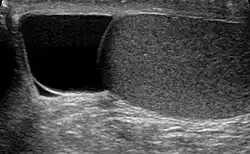

| Ultrasound of a testicle (grey) and a spermatocele (black). | |

The primary care physician may diagnose and manage benign causes of scrotal masses such as hydrocele, varicocele and spermatocele. However, if a "must not miss" diagnosis related to testicular masses such as testicular torsion, epididymitis, acute orchitis, strangulated hernia and testicular cancer is suspected, the family physician must refer to a urologist.[19] Finding a painless, cystic mass at the head of the epididymis that is clearly separate from the testicle can indicate a spermatocele. Shining a light through the mass, a process known as transillumination, can also help differentiate between a fluid-filled cyst and a tumor, which would not allow as much light to pass.[20] If uncertainty exists, ultrasonography of the scrotum can confirm the presence of a spermatocele.[7] The location and history of any scrotal masses are crucial in determining whether or not the mass is benign or malignant.[21] Lab tests such as a complete blood count (CBC test) or urine test can also be conducted to check for any possible infection or signs of inflammation.[22]

Spermatoceles come in varying sizes and shapes. Some spermatoceles are very small and can only be detected through an ultrasound. More commonly seen are spermatoceles that are a pea-sized lump. They tend to form above or behind a testicle and have a shape and size that looks like a pea. Larger growths have been reported to look similar to a third testicle and can be very discomforting.[22] For those who are affected with large spermatoceles, some have reported feeling pain, heaviness, and fullness in the affected testicle.[20]

Although the evidence and information for incidence of spermatoceles in children is lacking, there are general management guidelines for caregivers who may encounter spermatoceles in their children.[9] Epididymal cysts are typically benign in nature. However, caregivers should take note of any discomfort and symptoms in children, including but not limited to, erythema, scrotal edema or swelling.[9] Epididymal cysts appear in approximately 70% of boys who present as asymptomatic.[9] The diagnosis of epididymal cysts in children can be discovered upon physical examination and eventually confirmed via ultrasound.[9]

Upon physical examination, if a 'lump' is found during the testicular exam, further screening may be performed via ultrasound to eliminate testicular cancer.[18]